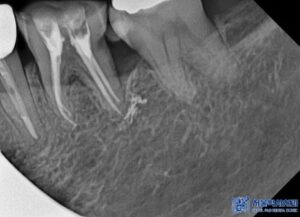

환자분도 MTA 신경치료를 통해

자연치아를 보존할 수 있도록

치료를 진행하였으며,

신경치료 마무리 후에는

크라운을 제작하였습니다.